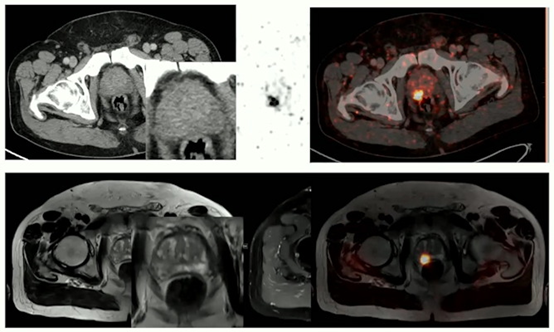

在埃森,PET/MRI在腫瘤成像中的應用最為廣泛,尤其是前列腺成像。PET/CT可以并且可以有效地用于檢測前列腺切除術后的生化復發,但在手術前,PET/MRI在檢測原發腫瘤以及已擴散到周圍組織的癌癥方面具有優勢。

Umutlu說,PET/MRI在前列腺癌術前成像方面比PET/CT更有效。